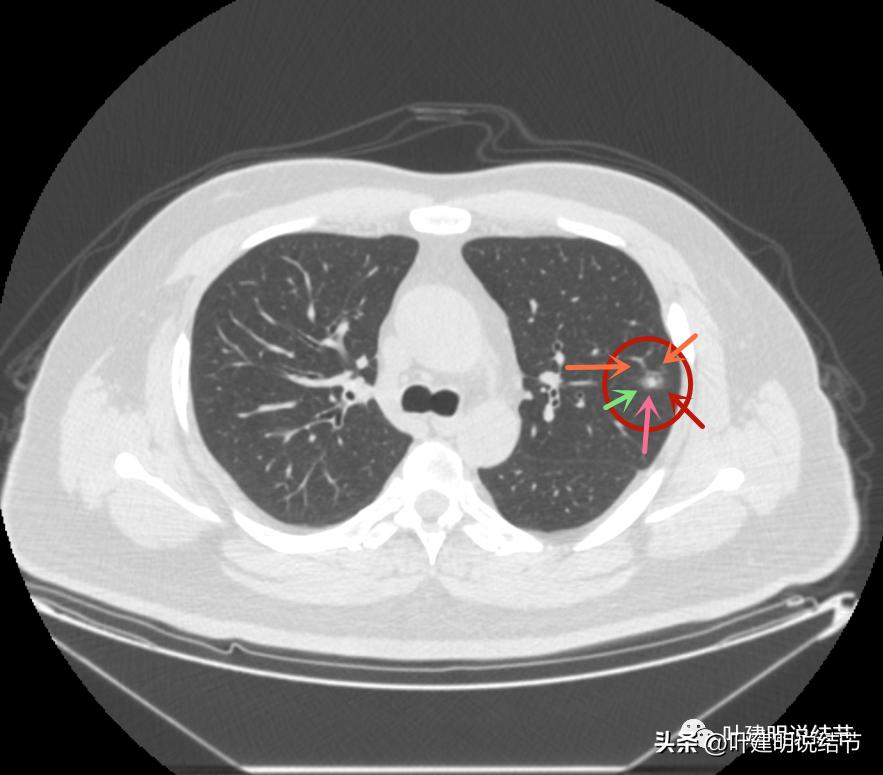

毛刺征(紫色箭头),微血管征(桔色箭头),实性点状成分(粉色箭头),整体轮廓较清(红色箭头)

血管弯征(桔色箭头)

血管进入

病灶3边缘部分的样子

感觉这两个病灶也是较为典型的恶性结节,但略不确定的是有的层面似乎有点像有卫星灶,再有就仍是这么多病灶集中在相对较小的区域内有点难以理解。